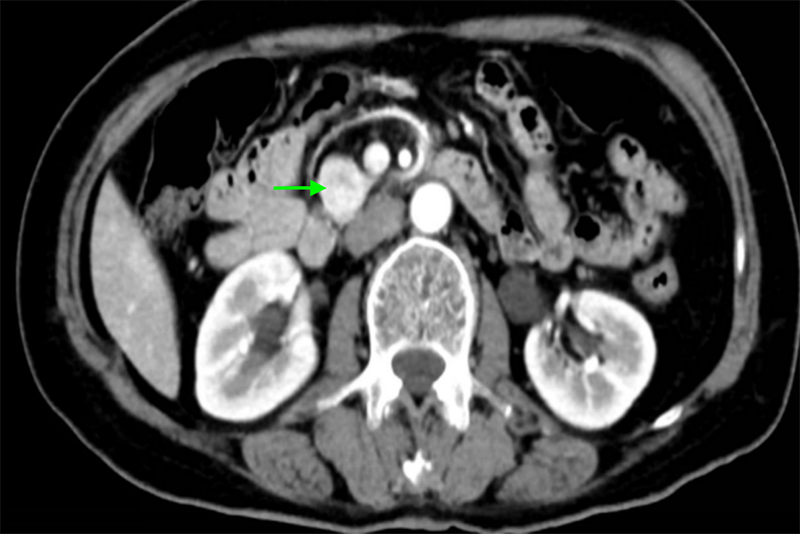

經(jīng)檢查,陳大嬸有低血糖癥狀、代謝性腦病,進(jìn)一步行PET/CT檢查及腹部增強(qiáng)CT檢查后考慮為胰島素瘤。內(nèi)分泌科立即組織肝膽胰外科、神經(jīng)內(nèi)科、內(nèi)分泌科、臨床營養(yǎng)科、麻醉科等多學(xué)科聯(lián)合診療,專家們討論后一致認(rèn)為陳大嬸的胰島素瘤有明確手術(shù)指征,于是轉(zhuǎn)入肝膽胰外科進(jìn)一步手術(shù)治療——腹腔鏡探查、胰腺鉤突腫瘤切除術(shù)。

專家團(tuán)隊(duì)進(jìn)行了精心的術(shù)前準(zhǔn)備,并制定了精細(xì)化麻醉方案。術(shù)中,肝膽胰腺外科手術(shù)團(tuán)隊(duì)參考術(shù)前CT資料及術(shù)中腔鏡超聲精確定位腫瘤,將胰島素瘤完整切除,整個手術(shù)過程時間僅為80分鐘,出血量僅為5ml。術(shù)后,患者血糖水平恢復(fù)到正常水平,認(rèn)知障礙逐步得到改善,一周后復(fù)查CT未見胰漏。出院前,陳大嬸體力、飲食、精神等方面完全恢復(fù)正常,已能和家人順利交流,終于擺脫了被誤解的慘痛經(jīng)歷。